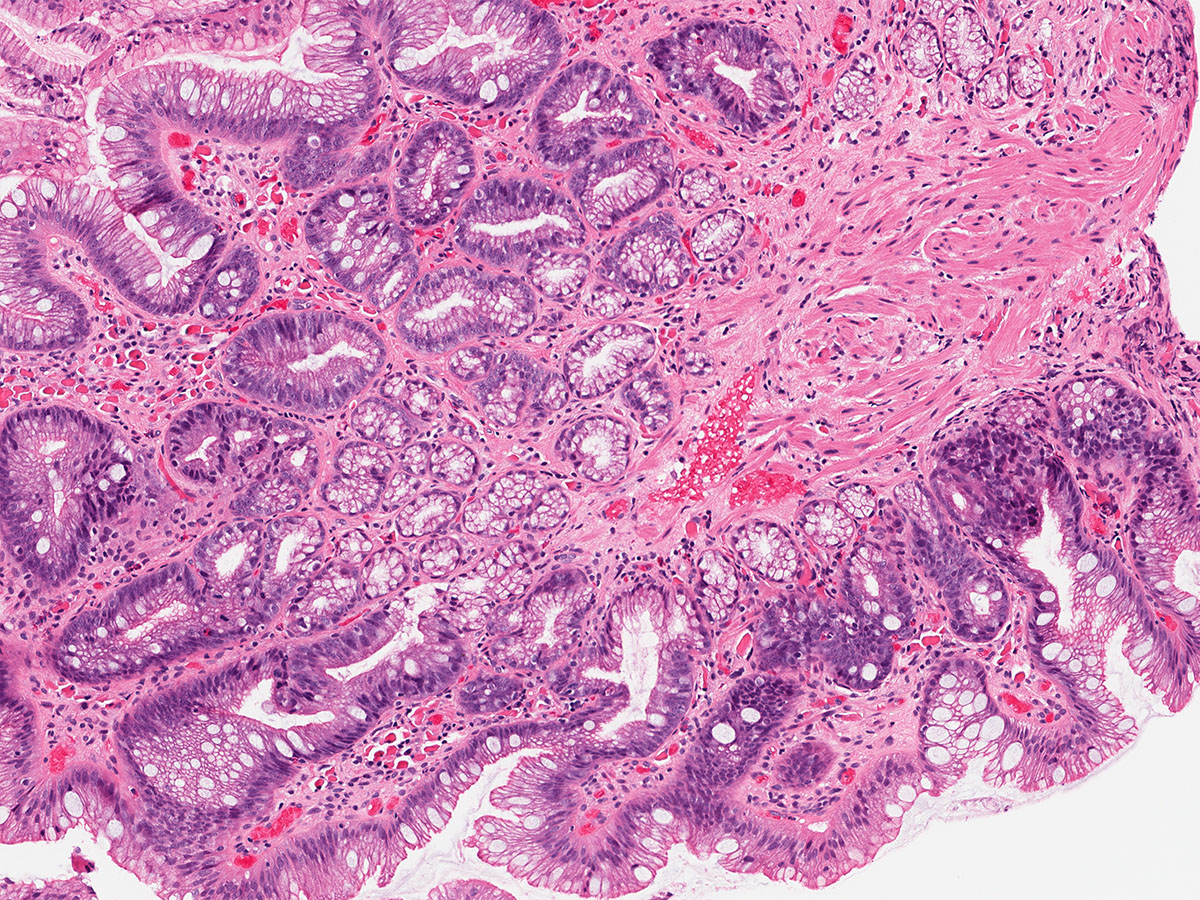

Cleveland Clinic Laboratories Industry Workshop with Jesse McKenney at ASCP 2017